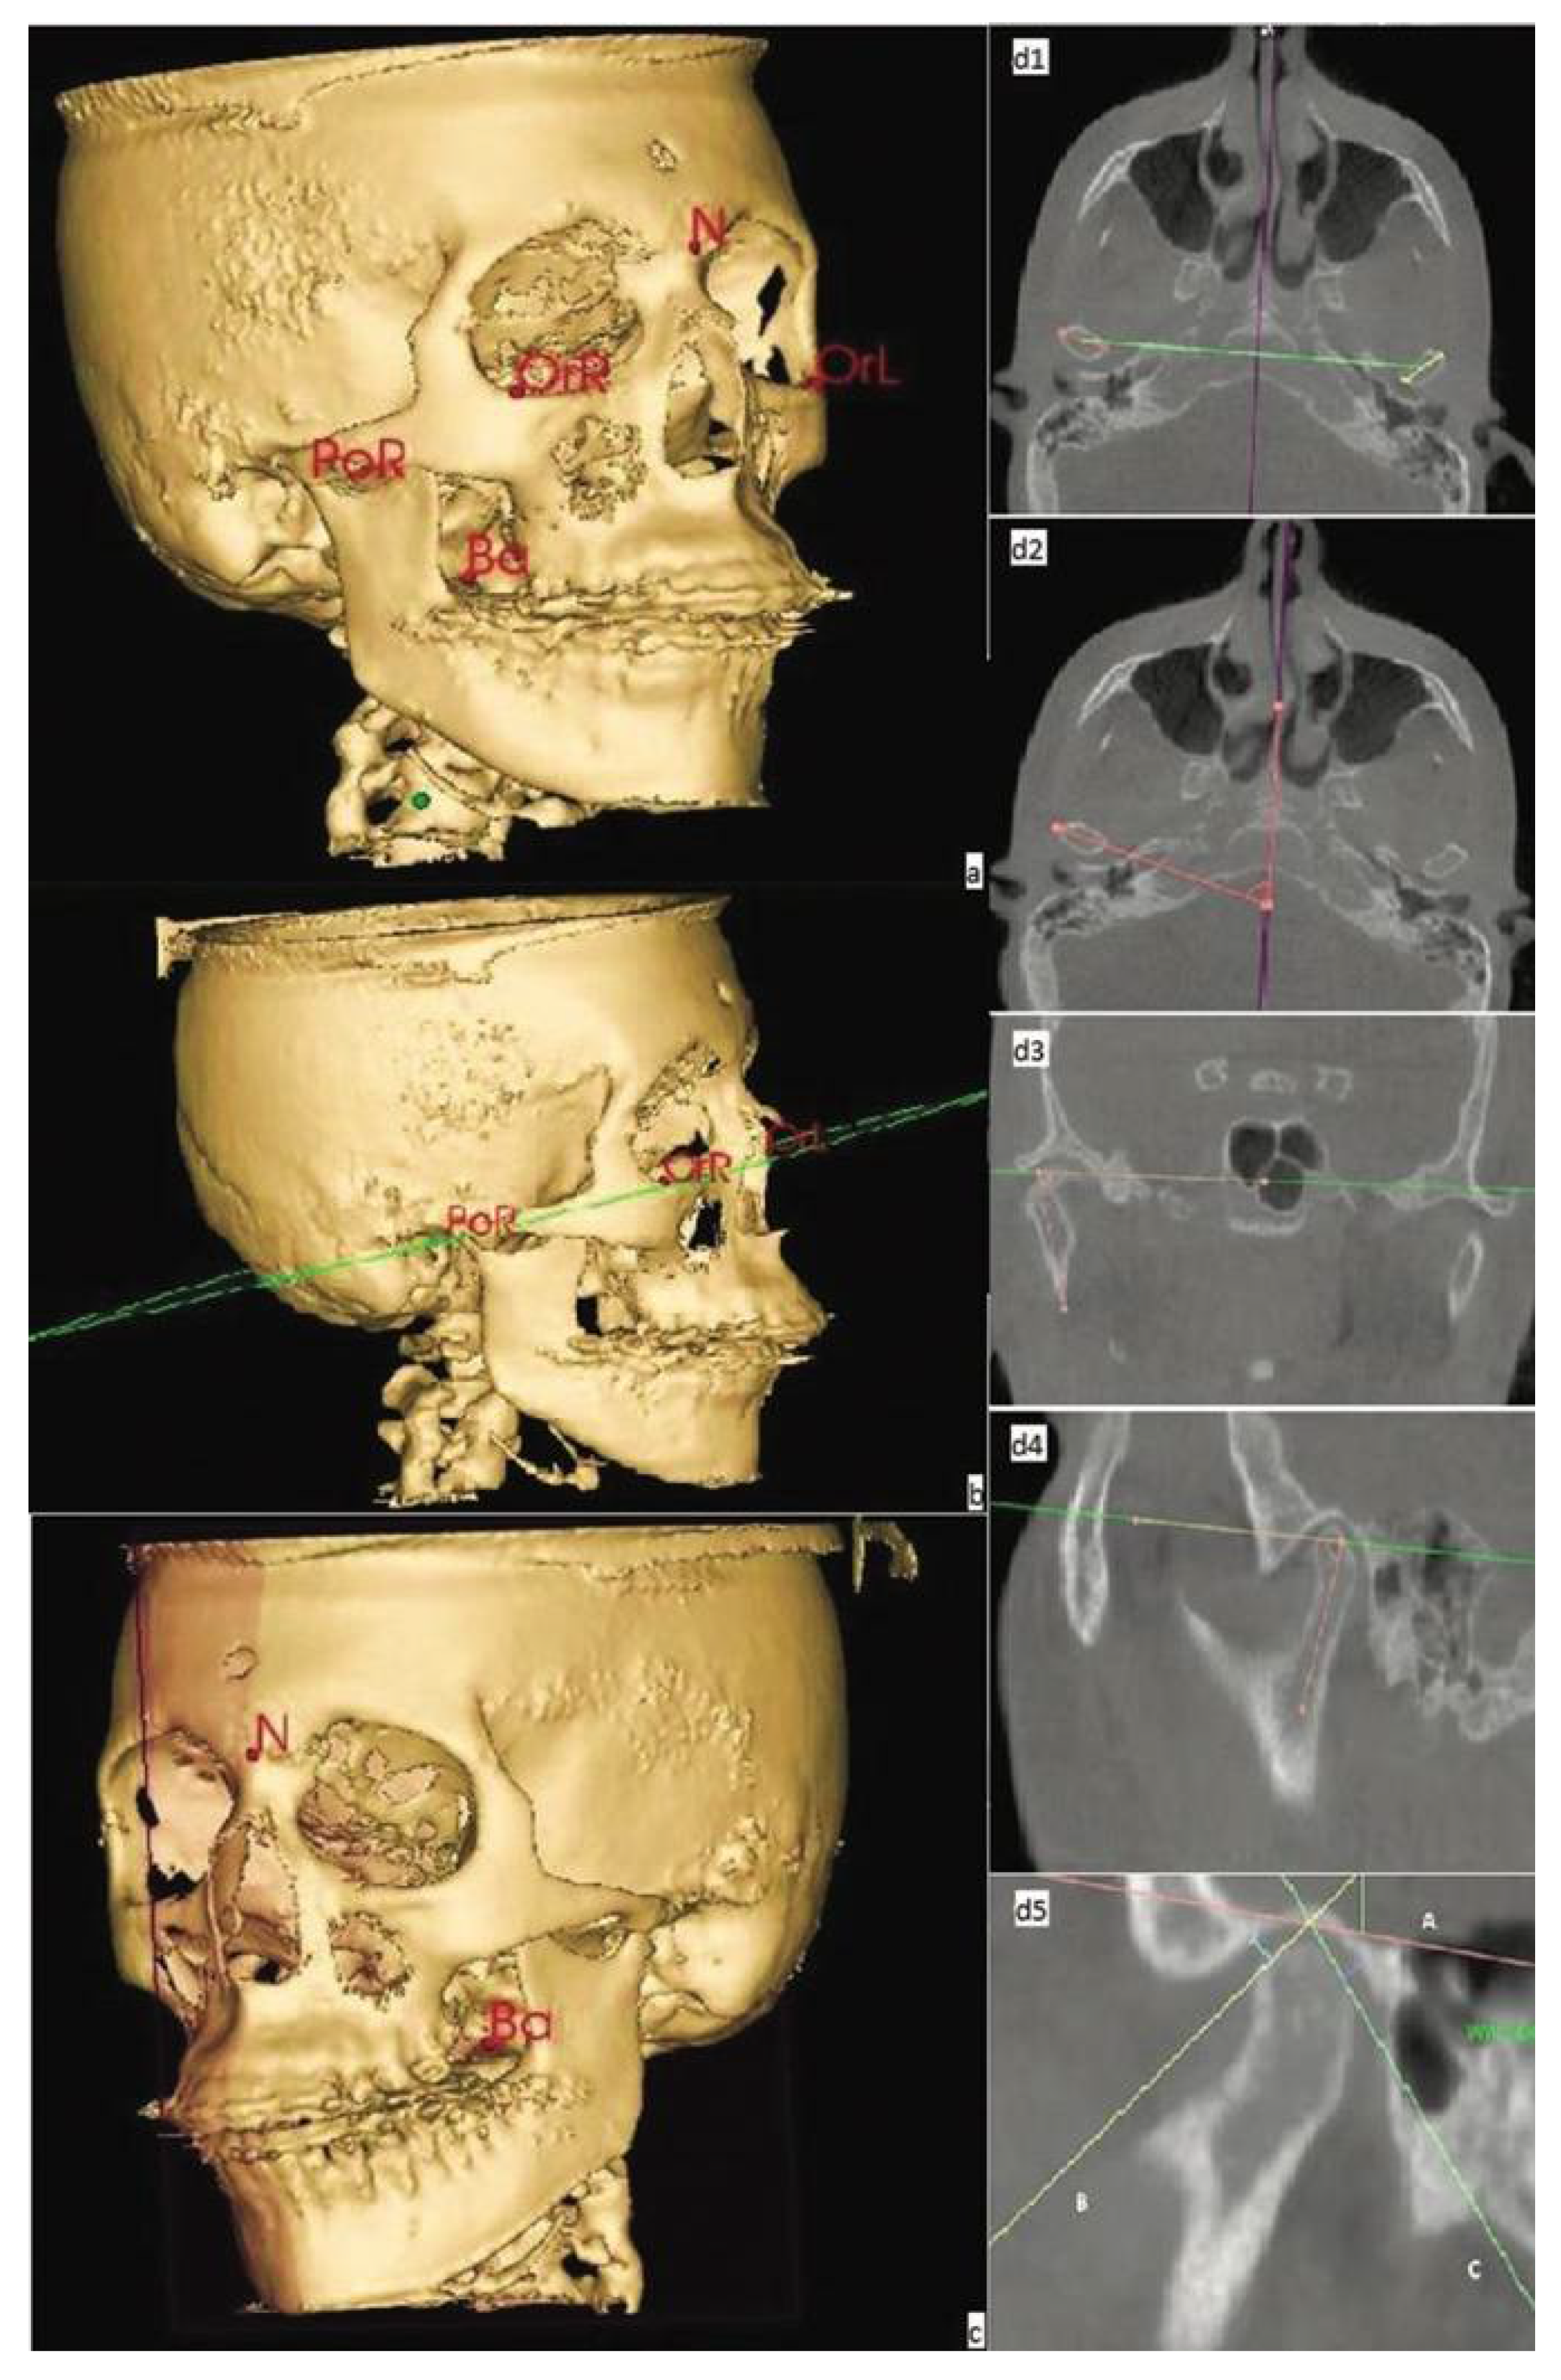

2.1. 3D Cephalometry

2.1.1. CBCT Assessment